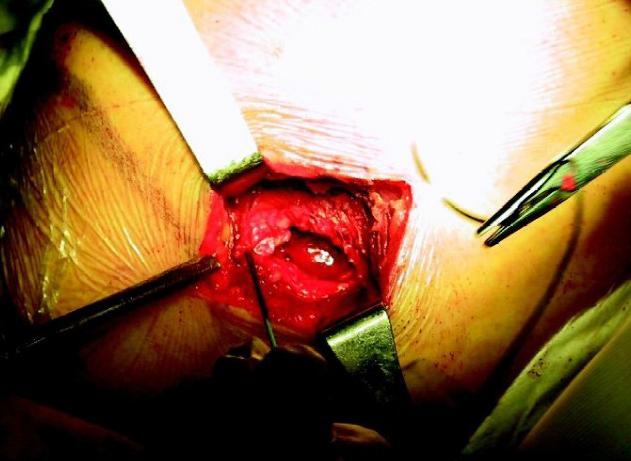

2. 小切口修复技术

随着关节镜技术在临床的应用,关节镜辅助小切口肩袖修复技术(mini-open技术)在90年代诞生了。

与传统切开手术相比,小切*技口**术不但切口小了,而且术中还能保留我们的三角肌止点,使得手术的成功率得到了提高。

小切口辅助开放手术 图片来源于网络,侵删